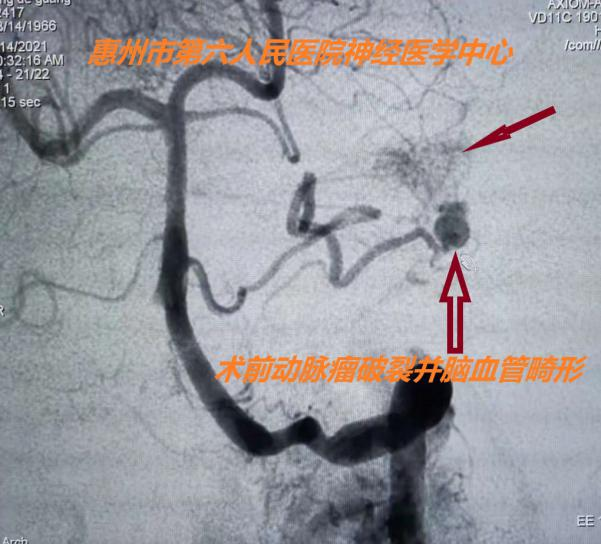

7時40分,患者轉(zhuǎn)運至六院急診科,病情進一步惡化,出現(xiàn)自主呼吸暫停,急診科立即對患者進行氣管插管,使用呼吸機輔助呼吸,患者生命體征稍穩(wěn)定后,為了進一步明確患者發(fā)病原因,由神經(jīng)外科醫(yī)生護送患者行急診全腦血管造影術(shù),結(jié)果顯示:患者左側(cè)小腦前動脈動脈瘤破裂且仍有出血、左側(cè)小腦前動脈動靜脈畸形。

患者生命垂危,搶救刻不容緩!神經(jīng)外科主任醫(yī)師余永強、副主任醫(yī)師劉立國立即帶領(lǐng)介入團隊為患者進行左側(cè)小腦前動脈動脈瘤栓塞+左側(cè)小腦前動脈動靜脈畸形栓塞術(shù)。介入手術(shù)難度大、風(fēng)險高,主刀醫(yī)生需要打起十二分的精神,“穩(wěn)如泰山”“一針到位”。經(jīng)過介入團隊和介入室全體醫(yī)護的認(rèn)真努力,手術(shù)取得成功,患者左側(cè)小腦前動脈瘤及畸形的動靜脈完全栓塞,患者轉(zhuǎn)入神經(jīng)外科重癥監(jiān)護室繼續(xù)治療。